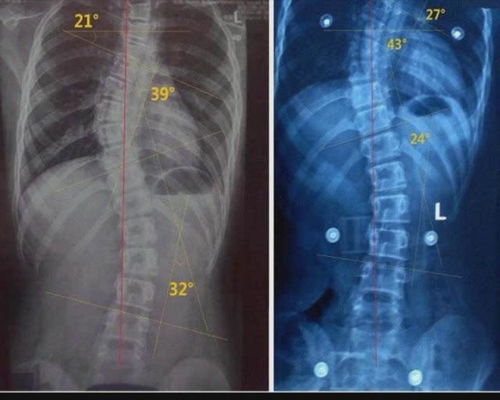

所以,脊柱側(cè)彎角度小于20度的女性可以放心的懷孕,平時要加強(qiáng)營養(yǎng),注意休息,但是脊柱彎曲超過20度到45度的患者,要到醫(yī)院進(jìn)行評估,在醫(yī)生的指導(dǎo)下完成,不能冒風(fēng)險。

如果側(cè)彎角度45度以上,肯定是不適合懷孕的。

注意保養(yǎng)與休息避免懷孕加重脊柱的側(cè)彎就是可以的幾乎沒有危害,一般大于20度小于45度,妊娠全過程要在醫(yī)生的指導(dǎo)下完成,可以預(yù)見的是不僅需要冒一定的風(fēng)險,過程也將相當(dāng)辛苦們?nèi)绻麄?cè)彎角度在45度以上,肯定是不適合懷孕的,保守治療只能減輕身體癥狀或阻止進(jìn)一步發(fā)展側(cè)彎